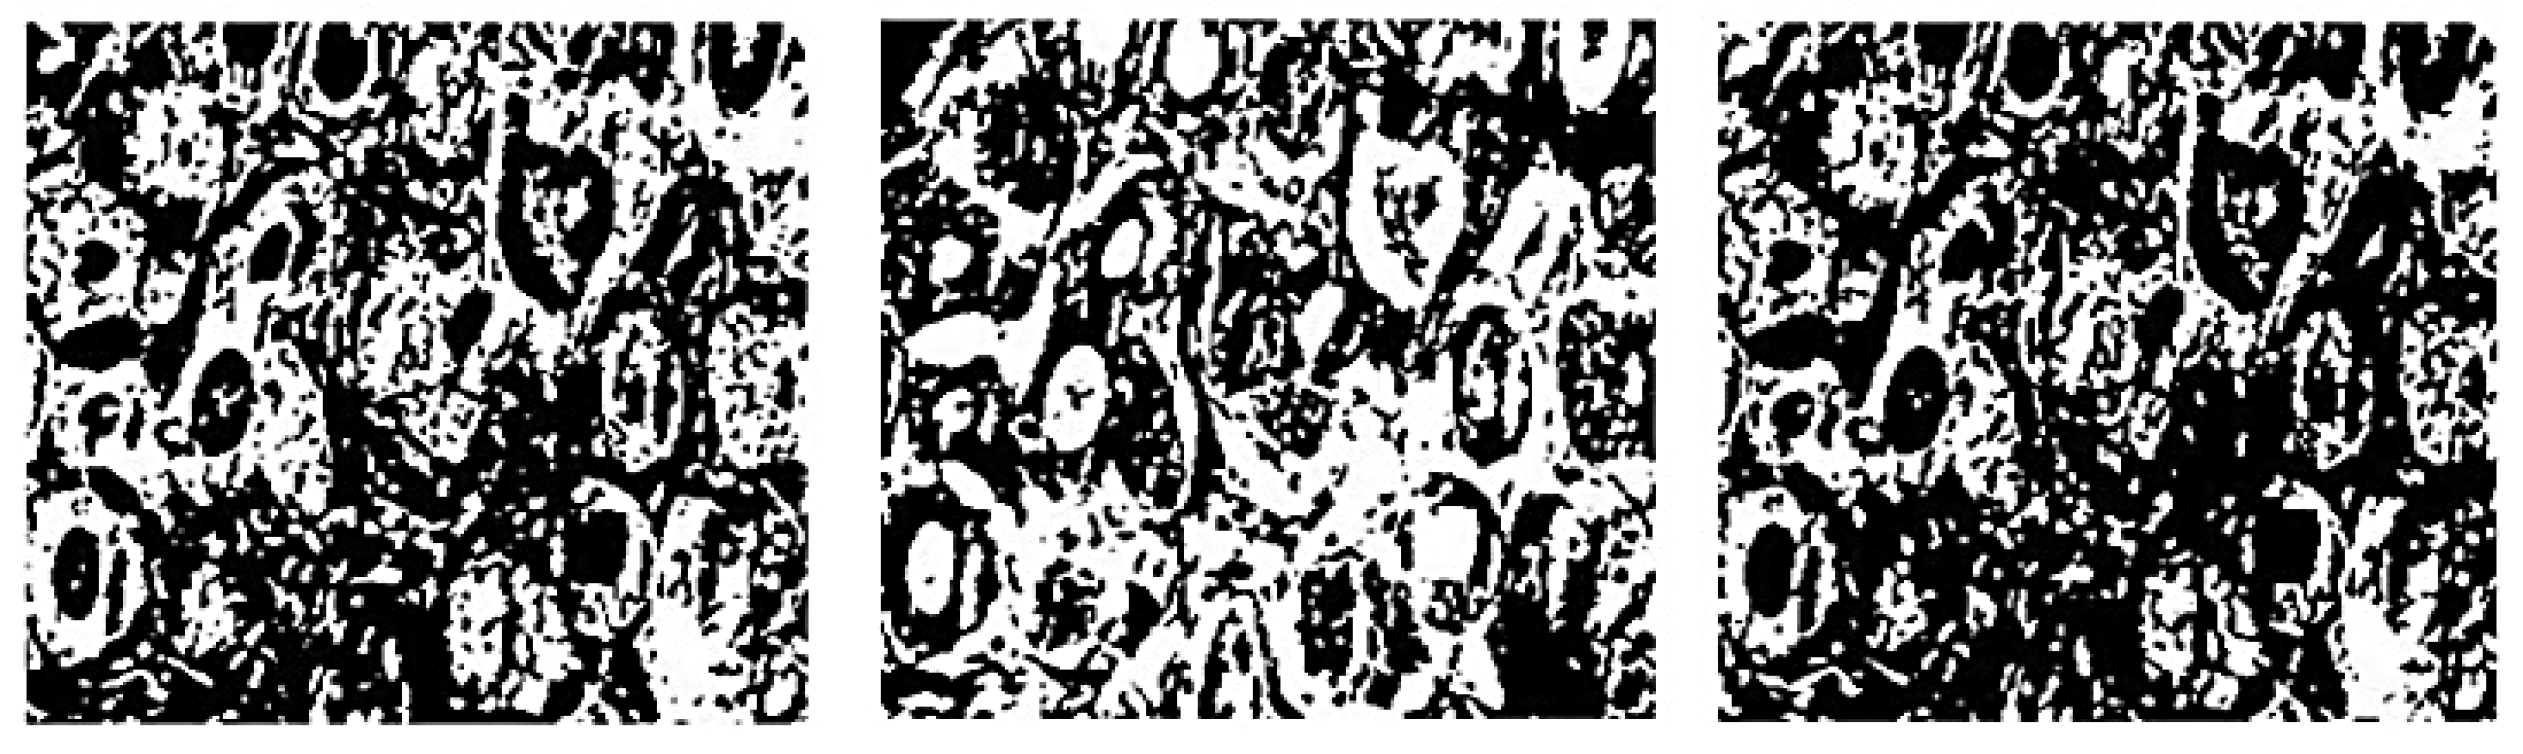

AI may be used to overcome the constraints of screening mammography in a variety of ways, including as a detection tool with a human reader. Human-like or superhuman performance has been shown in studies employing different algorithms under circumstances that are sometimes very realistic [103]. Vaka AR [104] using a dataset taken from M.G Cancer Hospital and Research Institute, Visakhapatnam, India. There are 8009 histopathological picture samples from over 683 patients in the collection, with different magnification levels. This researcher proposed novel technique called Deep Neural Network with Support Value (DNNS) is used to improve picture quality and correct other performance factors. The experimental results are presented in Figure 13, the proposed segmentation is illustrated as shows in Figure 14.

Figure 13.

The experimental result. Segmented images of proposed DNNS method [104].

Figure 14.

Comparison of result by segmentation and proposed segmentation [104].